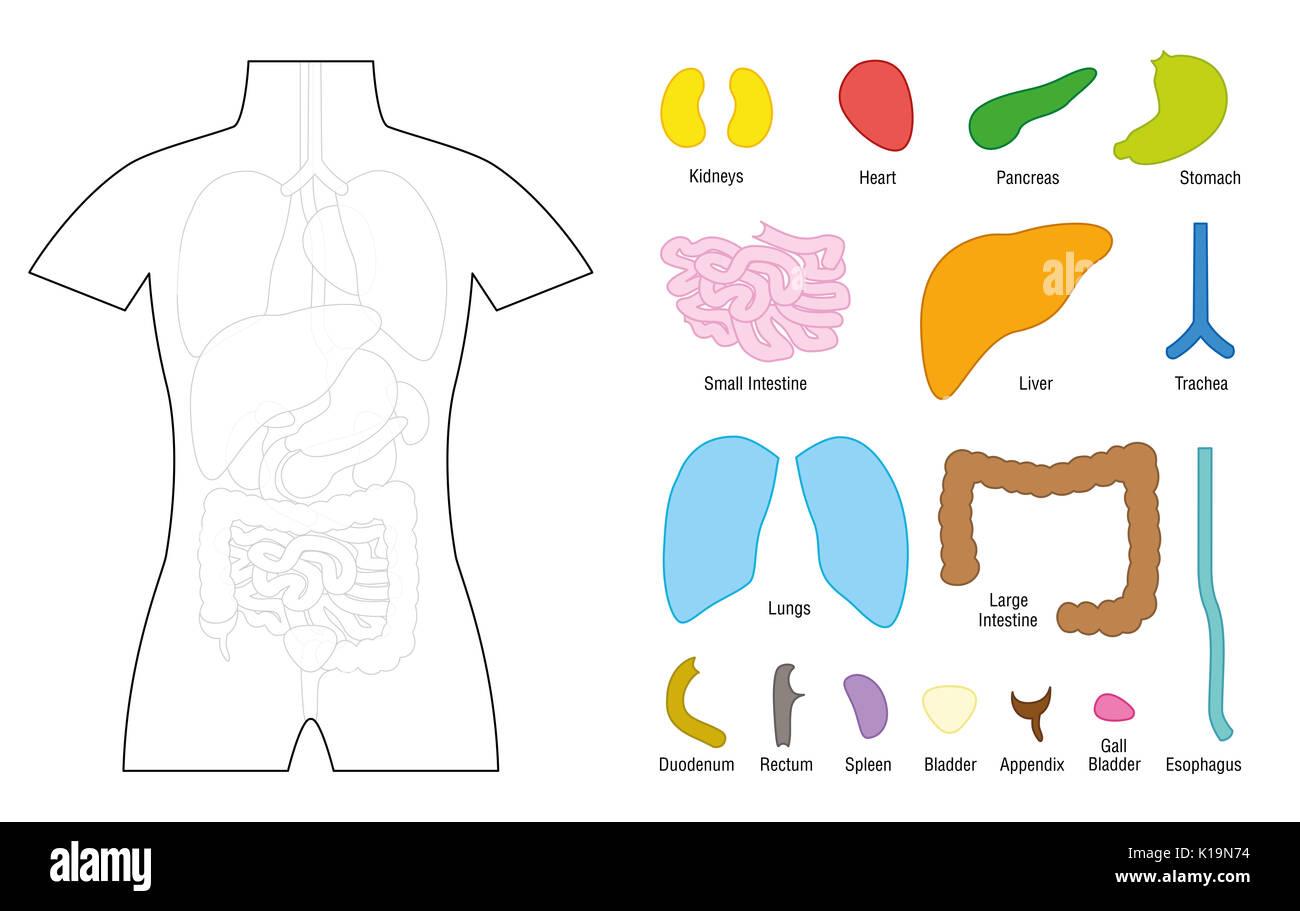

Internal organs - puzzle template for educational use - cut the organs out and put it on the right place of the human body, or color it in. Stock Photohttps://www.alamy.com/image-license-details/?v=1https://www.alamy.com/internal-organs-puzzle-template-for-educational-use-cut-the-organs-image155722200.html

Internal organs - puzzle template for educational use - cut the organs out and put it on the right place of the human body, or color it in. Stock Photohttps://www.alamy.com/image-license-details/?v=1https://www.alamy.com/internal-organs-puzzle-template-for-educational-use-cut-the-organs-image155722200.htmlRFK19N74–Internal organs - puzzle template for educational use - cut the organs out and put it on the right place of the human body, or color it in.